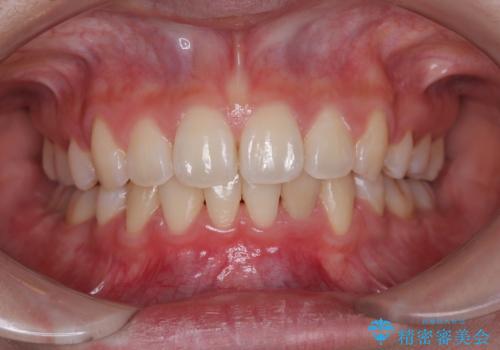

【審美装置】前歯のがたがたを治したい

担当医 河口智英

【審美装置】前歯をきれいにしたい

前歯を綺麗にしたい 部分矯正とセラミック治療

前歯のデコボコをインビザラインできれいに整える